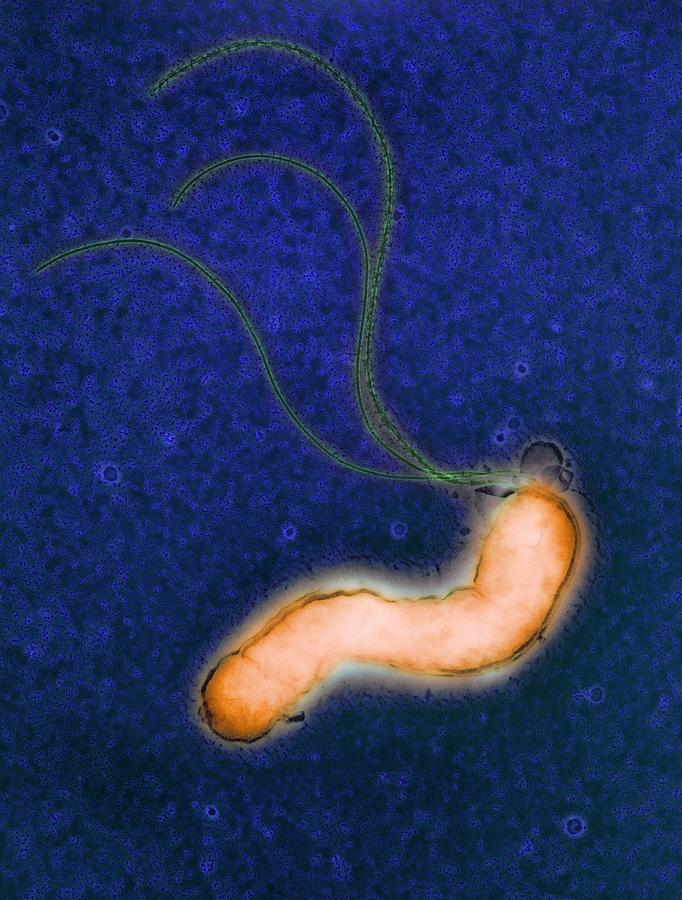

Кампилобактер фетус: патогенез и инфекции